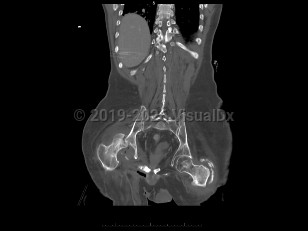

Septic arthritis

An infection of a joint most frequently caused by bacteria (although fungi, parasites, and mycobacteria may also rarely cause this infection).

This infection occurs most commonly as a result of hematogenous seeding of the joint in the setting of bacteremia. A joint may be inadvertently inoculated with a pathogen at the time of surgery or trauma. In some patients, a severe soft tissue infection may spread to involve a nearby joint.

Common pathogens responsible for this infection include Staphylococcus aureus, Streptococcus species, gram-negative bacilli, and Neisseria gonorrhoeae.

Risk factors for this infection include old age, diabetes mellitus, recent joint surgery or procedure, skin infection, the presence of a prosthetic joint, or immunosuppression. Patients with rheumatoid arthritis or who abuse intravenous (IV) drugs are also at increased risk for this infection.

Patients present with a swollen, warm, stiff, and painful joint. Fever may be present. The majority of the time, a single joint (usually the knee) is involved. Symptoms develop over 1-2 weeks. If the infection is caused by N gonorrhoeae, patients classically also present with a rash and tenosynovitis. If the infection is due to fungi or mycobacteria, the symptoms may be subtler and may worsen more gradually.

Diagnosis can be made by arthrocentesis. Joint fluid should be sent for analysis including cell count, microscopic analysis for crystals, Gram stain, and bacterial culture. Additional cultures of the joint fluid can be obtained if an atypical pathogen is suspected by history or examination.

Treatment requires drainage of the joint (surgically or by repeated needle aspiration) in combination with antimicrobial therapy.